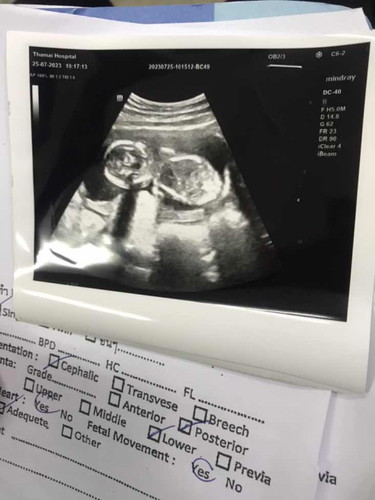

ดูแค่ภาพในจอไม่ทราบได้ค่ะ คุณแม่ต้องเอาตัวเลขที่หมอแจ้ง เช่น นน. ความยาว แล้วเทียบเกณฑ์ในแต่ละสัปดาห์ ก็จะทราบว่าเล็กไปหรือไม่

ไปซาวทีไรคุณหมอบอกตามเกณฑ์ ก็อุ่นใจแล้วค่ะบ้านนี้ หมอบอกทุกครั้ง ความยาว น้ำหนักแล้วเอามาเทียบตารางดูเองก็ได้ค่ะ

ลองดูตามตารางนี้นะคะ ถ้าตามน้ำหนักตามวีคก็ไม่ต้องกังวลคะ อาจจะมีเลยนิดหน่อยไม่เป็นไรคะ

น้ำหนักน้องเท่าไรคะ

น้ำหนักเท่าไรคะแม่